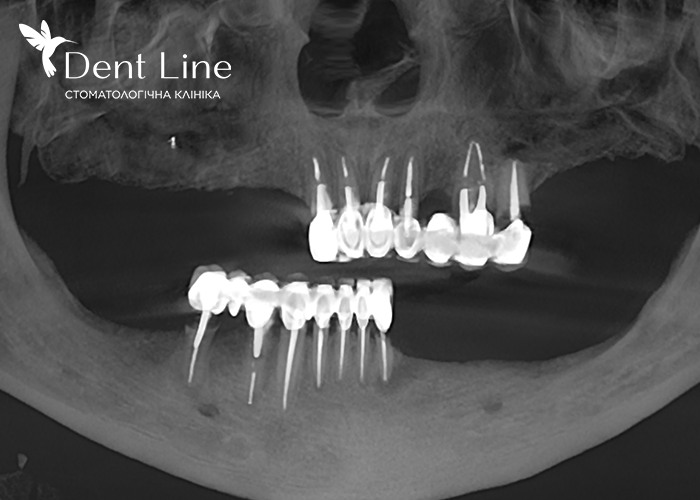

Зуби на фото BEFORE та, зокрема, на рентген-знімку в результаті хронічних запальних процесів, руйнувань тканин під коронками, підлягали виключно видаленню і подальшому встановленню імплантів:

Було проведене одномоментне видалення всіх зубів на верхній та нижній щелепі, після чого встановлено імпланти JDental (Італія) з негайним навантаженням.